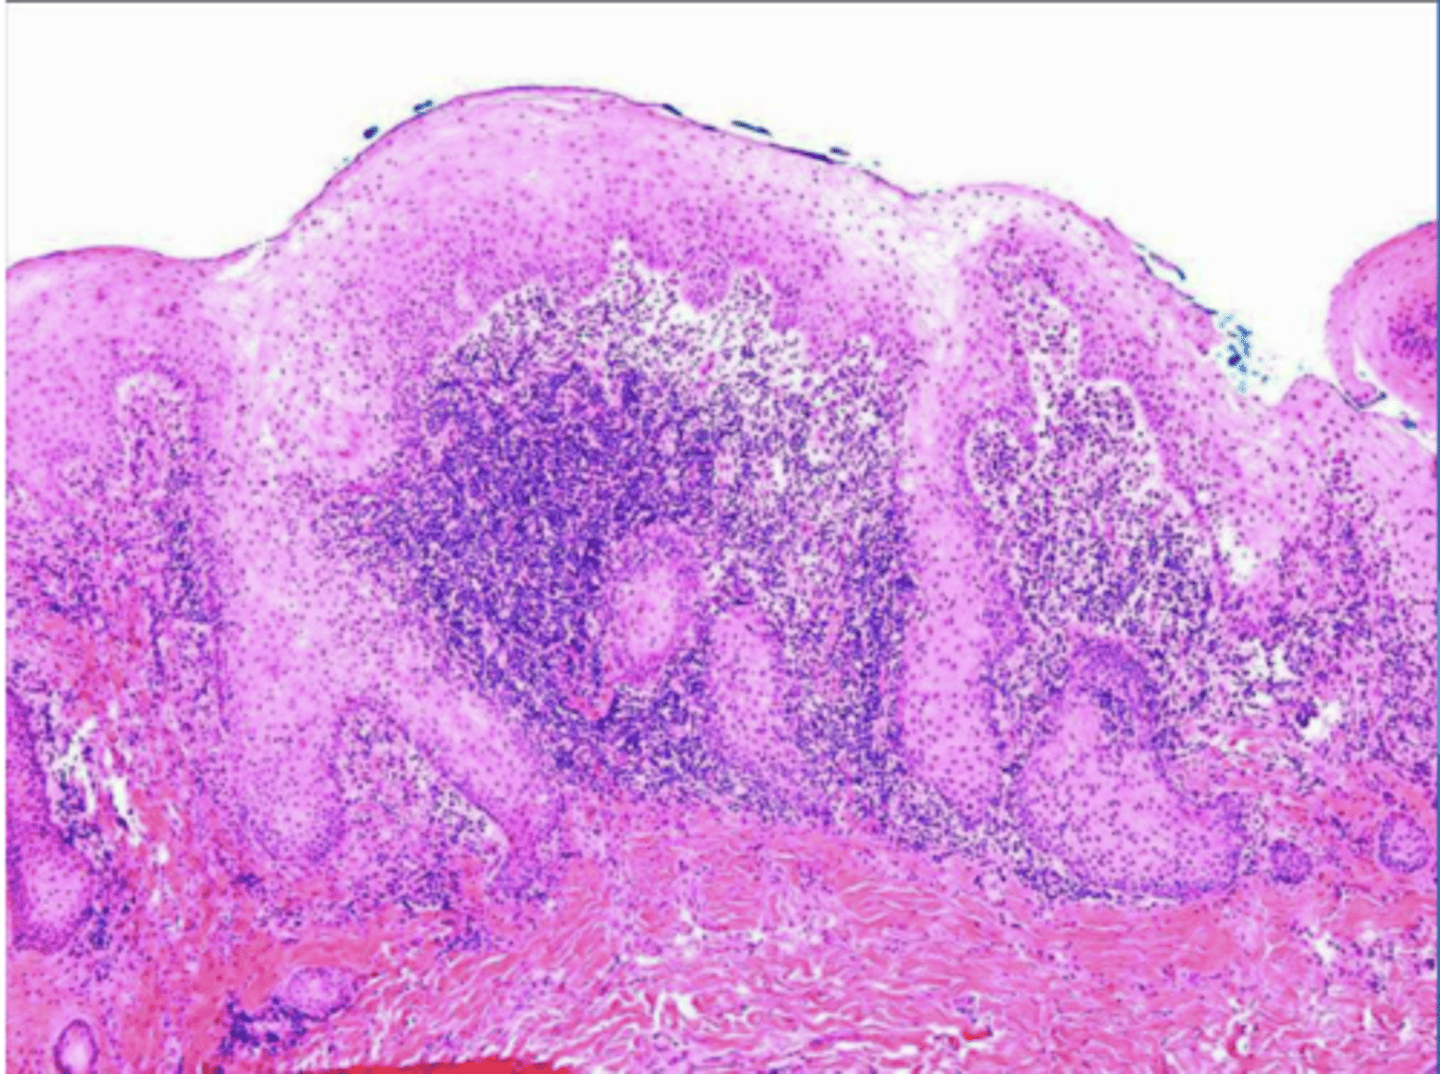

the following describe the histopathological features of what?

-numerous eosinophils

-inflammation of skeletal muscle

-granulation tissue

traumatice ulcerative granuloma